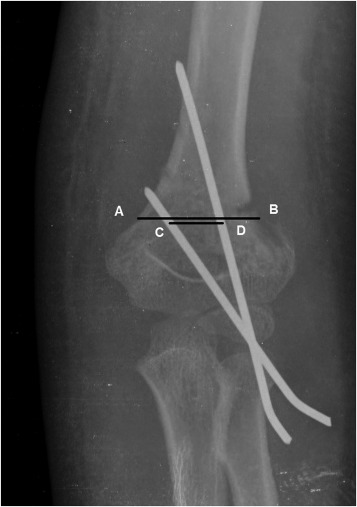

Direction of fracture displacement and fracture classification were assessed based on preoperative AP and lateral radiographs. Postoperative radiographic evaluation included true anterior-posterior radiograph and lateral radiograph of the elbow. Postoperative digital standard radiographs obtained after pin fixation at 3–4-week and 3-month follow-ups were postoperatively reviewed to determine LOR (Fig. 1 ).

Fig. 1

Fig. 1.

(A) Preoperative AP radiograph of type III supracondylar fracture. (B, C) Immediate postoperative AP and lateral radiographs revealing good reduction. Note medial wall comminution. (D, E) Radiographs taken at 4-week follow-up before pin removal showing reduction loss in coronal and sagittal planes. Red line indicates loss of reduction regarding the anterior humeral line.